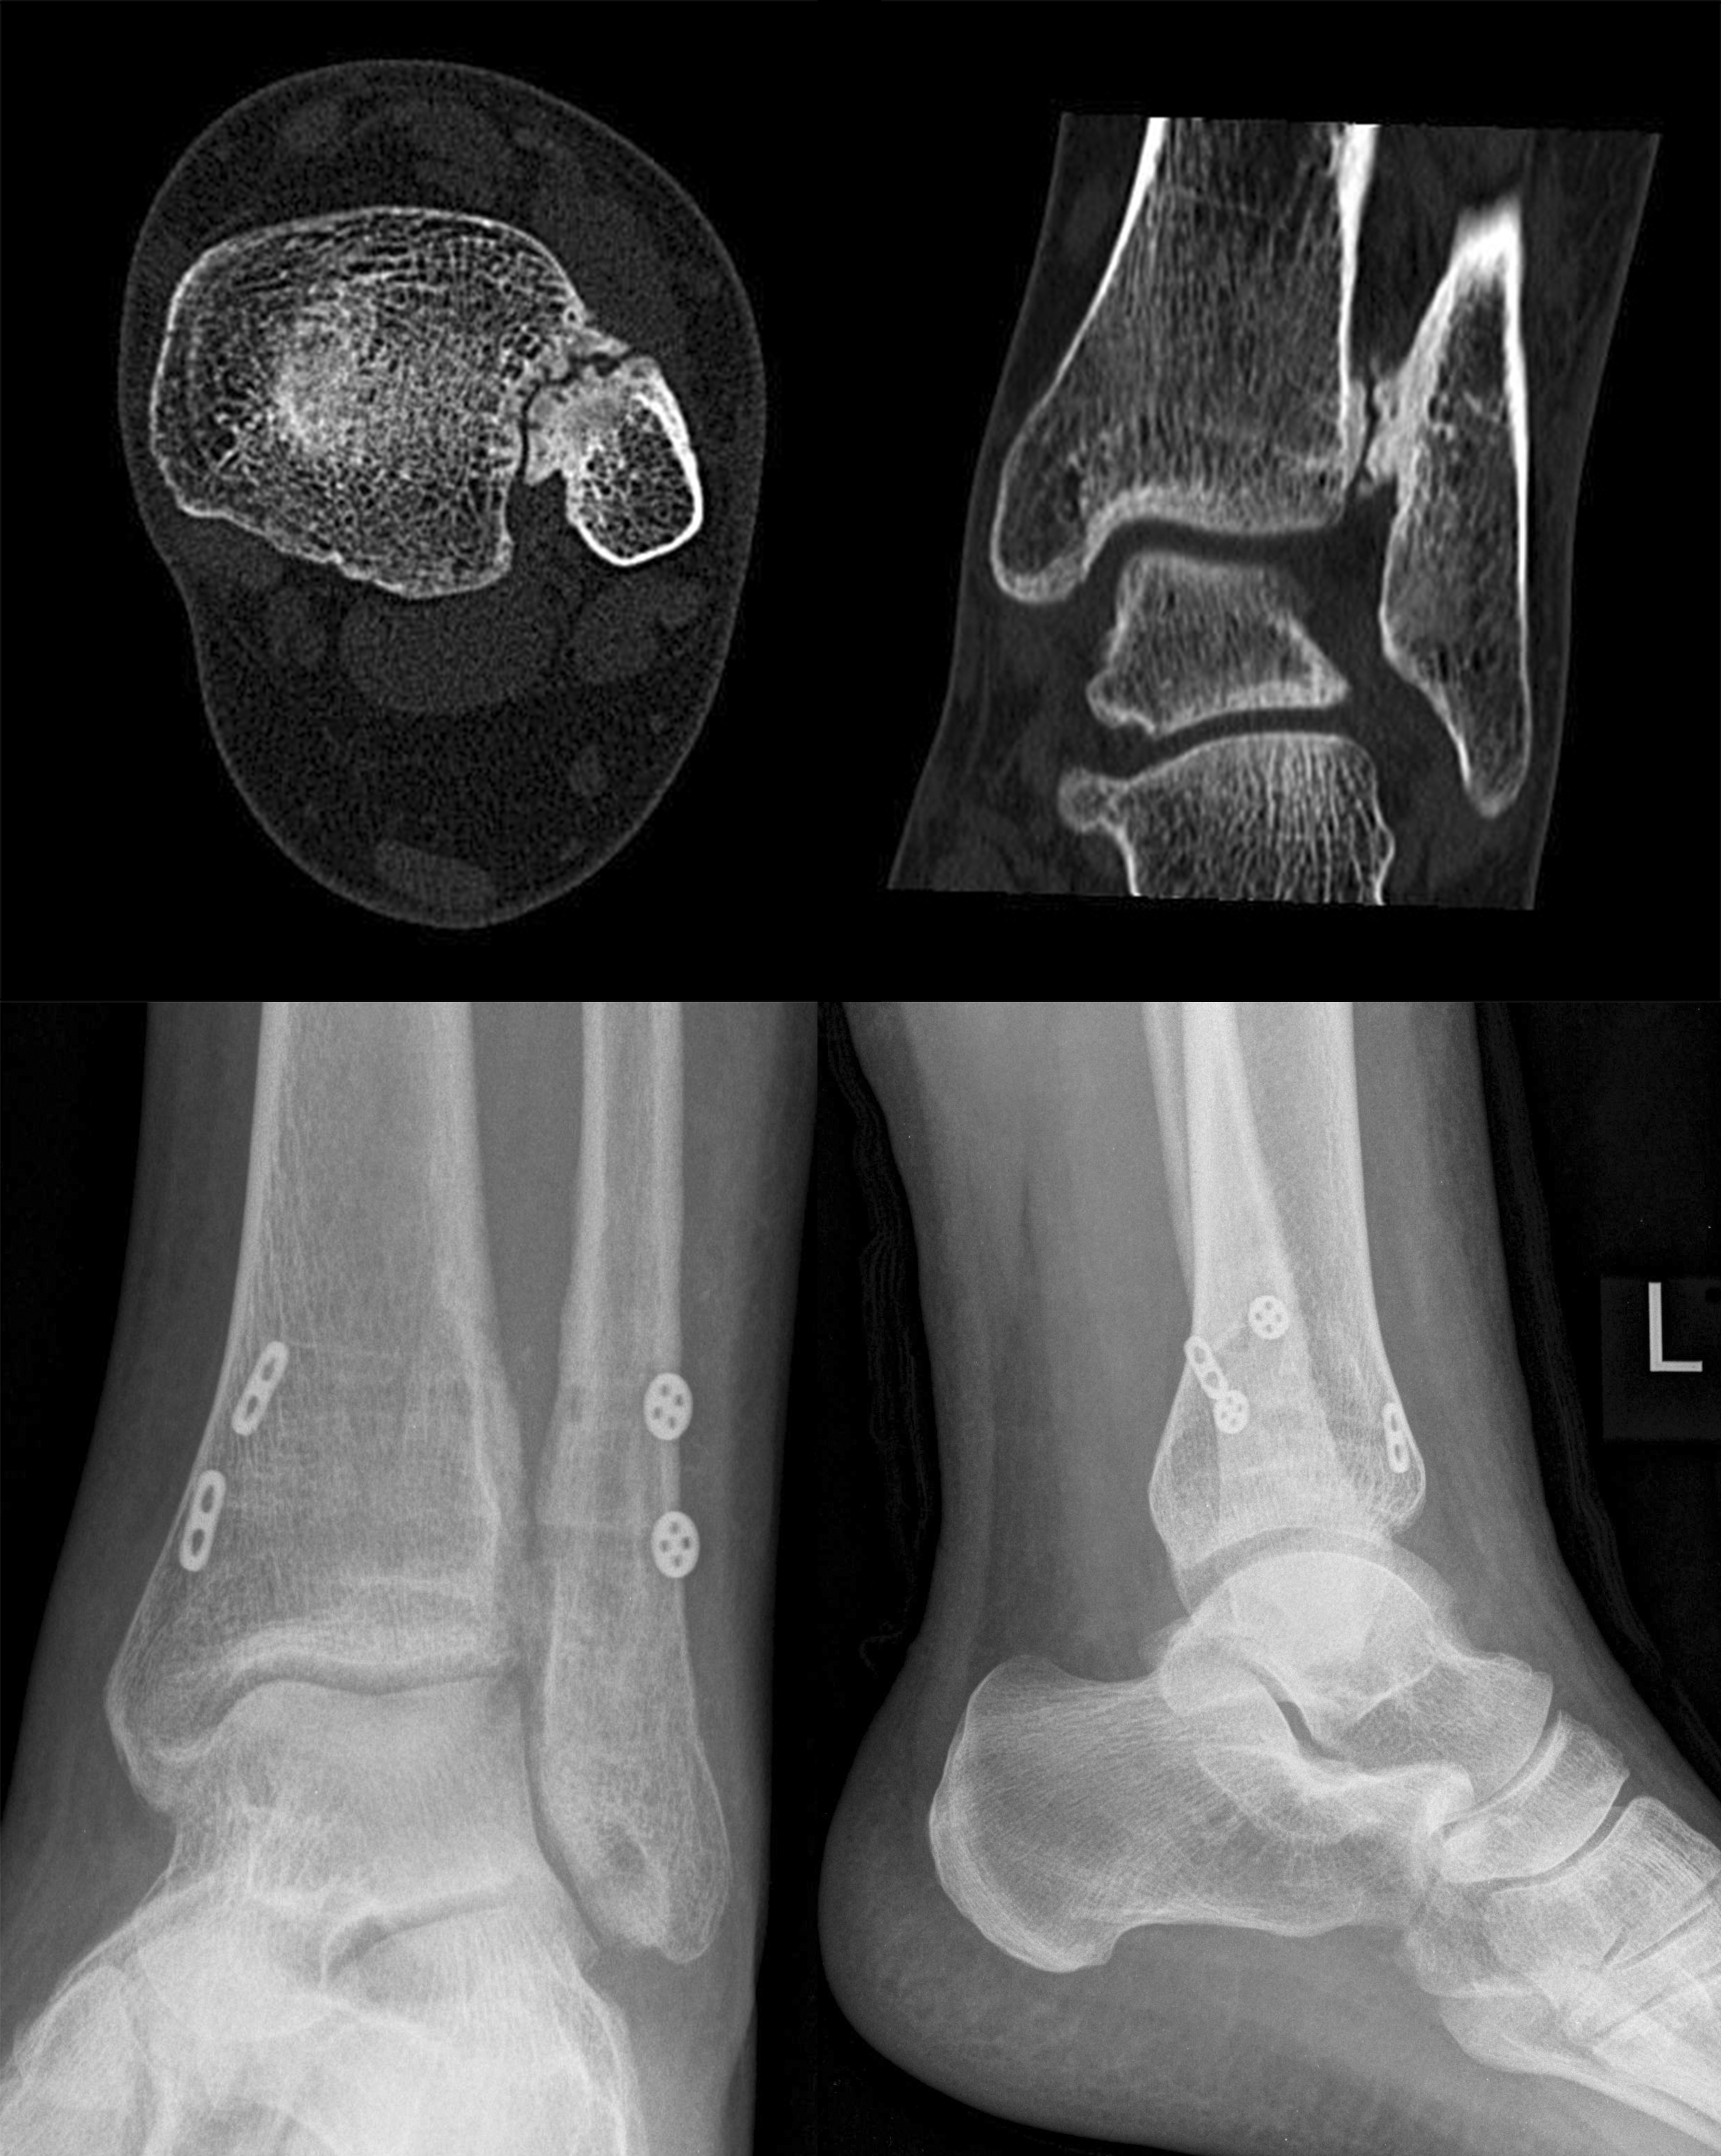

Die CT-Diagnostik erlaubt eine kritischere Beurteilung des DTFG. Die Wertigkeit zur Beurteilung von Syndesmosenverletzungen wurde in diversen Studien untersucht. Die Kongruenz im distalen Tibiofibulargelenk sollte in den axialen Schichten beurteilt werden 39. Aufgrund der hohen physiologischen Varianz, ist ein Seitenvergleich empfehlenswert (Abb. 5). So können die anteroposteriore Translation, Rotation und Verkürzung des betroffenen DTFG im Vergleich zum gesunden DTFG verglichen werden 40.